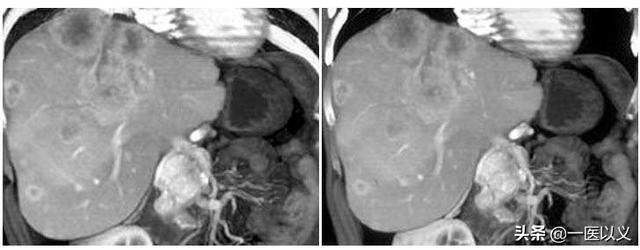

La plupart des hémangiomes caverneux sont découverts fortuitement par échographie lors d'un examen physique. Les lésions typiques présentent des images plus caractéristiques à l'échographie, au scanner et à l'IRM, et le diagnostic qualitatif n'est pas difficile. L'échographie et la tomodensitométrie permettent d'obtenir un rehaussement précoce et tardif, tandis que l'imagerie par résonance magnétique (IRM) T2 montre un "signe d'ampoule" (ci-dessous).